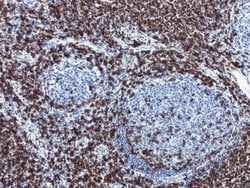

CD3 epsilon is part of the CD3 subunit complex which is crucial in transducing antigen-recognition signals into the cytoplasm of T cells and in regulating the cell surface expression of the TCR complex. T cell activation through the antigen receptor (TCR) involves the cytoplasmic tails of the CD3 subunits CD3 gamma, CD3 delta, CD3 epsilon and CD3 zeta. These CD3 subunits are structurally related members of the immunoglobulins super family encoded by closely linked genes on human chromosome 11. The CD3 components have long cytoplasmic tails that associate with cytoplasmic signal transduction molecules and this association is mediated at least in part by a double tyrosine-based motif present in a single copy in the CD3 subunits. CD3 may play a role in TCR-induced growth arrest, cell survival and proliferation. The CD3 antigen is present on 68-82% of normal peripheral blood lymphocytes, 65-85% of thymocytes and Purkinje cells in the cerebellum. It is never expressed on B or NK cells. Decreased percentages of T lymphocytes may be observed in some autoimmune diseases. The genes encoding the CD3 epsilon, gamma and delta polypeptides are located on chromosome 11. Defects in this gene are associated with T cell immunodeficiency and has been linked to Type 1 Diabetes deficiency in women.Specifications

| Immunocytochemistry, Immunofluorescence, Immunohistochemistry (Paraffin) | |